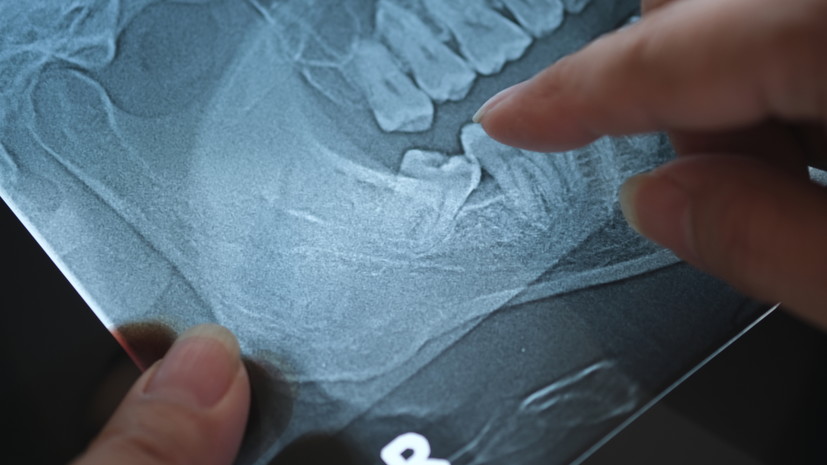

Ортодонт Маркова назвала мифом влияние зубов мудрости на асимметрию лица

В беседе с РИАМО эксперт отметила, что скелетная асимметрия формируется в детстве и зависит от других факторов.

Также зубы мудрости не оказывают давления, которое способно сместить зубной ряд вперёд, добавила врач.

«Поэтому мы не рекомендуем удалять их «на всякий случай». Основанием для удаления должны быть именно клинические показания», — сказала Маркова.